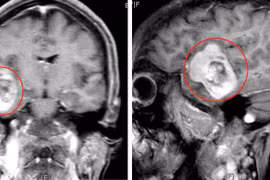

Một thiếu nữ 14 tuổi, mắc hội chứng Von Hippel-Lindau - một bệnh lý di truyền gây rối loạn mạch máu trong cơ thể, dẫn đến các u nguyên bào mạch máu ở não, thận, tụy và tủy sống.

Đau đầu triền miên, tình trạng đau đầu mạnh, tần suất nhiều, chị L. 42 tuổi (Ninh Bình) đi khám bất ngờ phát hiện khối u não nằm ở vị trí sâu nhất trong não.